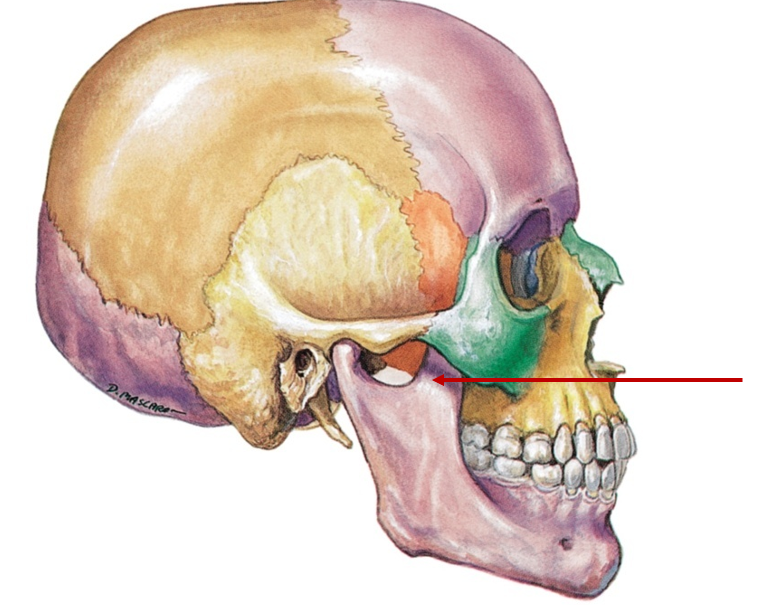

Maxilla

Upper jaw

Mandible

Lower jaw

Mental foramen

Small hole near chin

Mandibular condyle

Rounded end at back, fits into skull, jaw movement

Coronoid process

Sharp, triangular projection, chewing